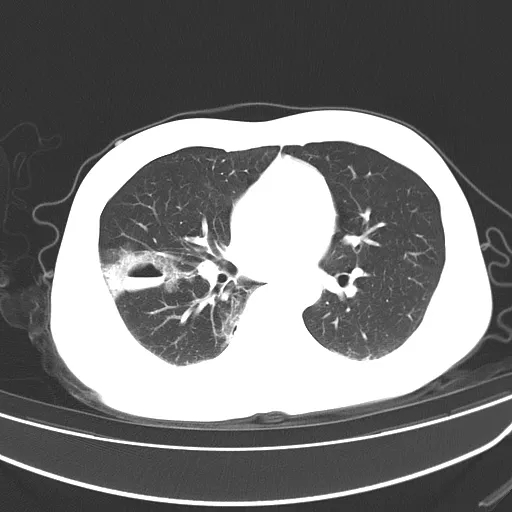

囊内充满血液者称为囊肿型;

f058a99be695f0a8a701ad21b0338792.jpg

创伤性假性肺囊肿多分布在肺野外周,可以伴骨折、肺挫伤、液气胸及纵隔、皮下气肿同时出现,囊肿内壁均匀、光滑,边缘多有斑片状渗出呈磨玻璃影或实变影改变,边界不清;短期内复查囊肿内密度容易变化,可以出现 3 种类型囊肿相互之间转化,但以空腔型转化为气液型囊肿或囊肿型转化为气液型囊肿较为多见

诊断创伤性假性肺囊肿需要有明确的外伤史此疾病多处于肺挫伤附近或中心,病变不稳定,短时间内病灶大小、形态均有明显改变。